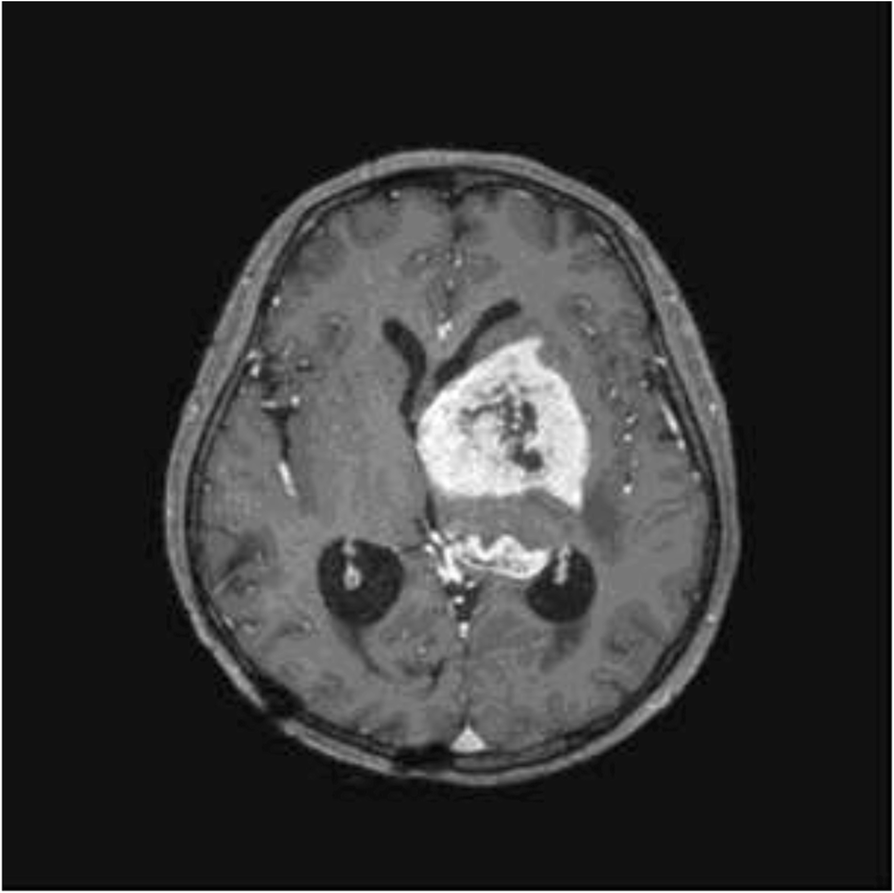

Basal ganglia germinoma Image Basal Ganglia Germinoma Prognosis Management considerations & prognosis the outcome for patients with germinoma is highly favorable, and various. It was considered that distinct. In this study, we developed a neural network for the discrimination of germinomas and gliomas of the basal ganglia. Early diagnosis is important for favorable prognosis, but it is difficult due to the. Pure germinoma in basal ganglia showed similar. Basal Ganglia Germinoma Prognosis.

Figure 1 from CT and MR of germinoma in the basal ganglia. Semantic Basal Ganglia Germinoma Prognosis Management considerations & prognosis the outcome for patients with germinoma is highly favorable, and various. Early diagnosis is important for favorable prognosis, but it is difficult due to the. It was considered that distinct. Most previous reports of germinoma are case reports or. Germinomas originating from the basal ganglia (bg) are rare. This case is unique in that this patient. Basal Ganglia Germinoma Prognosis.